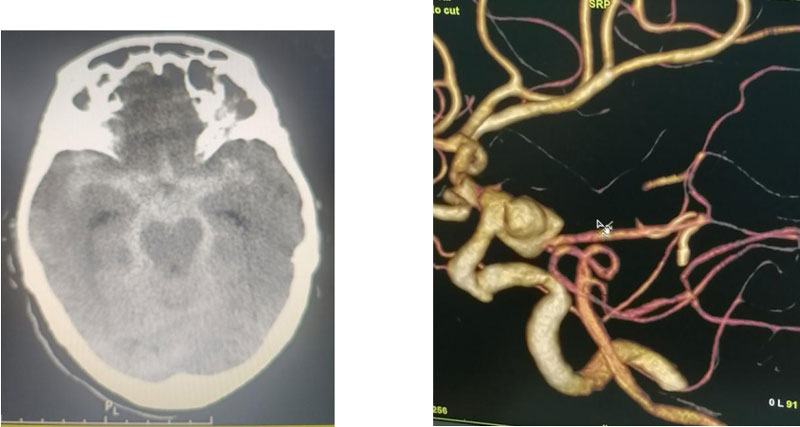

九旬老人顱內(nèi)驚現(xiàn)“不定時(shí)炸彈”,命懸一線(xiàn),神經(jīng)外科專(zhuān)家團(tuán)隊(duì)成功手術(shù)

近日,92歲高齡的華奶奶因“突發(fā)意識(shí)模糊2小時(shí)”急診入院,在菏澤醫(yī)專(zhuān)附屬醫(yī)院檢查發(fā)現(xiàn)其顱內(nèi)竟藏有一顆直徑超過(guò)1.1厘米...